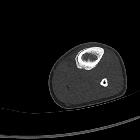

Morphological classification of periosteal reactions

More specific classification of periosteal reactions can be made to narrow the differential diagnosis.

- single layer

- multilayered

- solid

- spiculated

- perpendicular (hair-on-end)

- divergent (sunburst)

- sloping (velvet)

- disorganized/complex

- Codman triangle